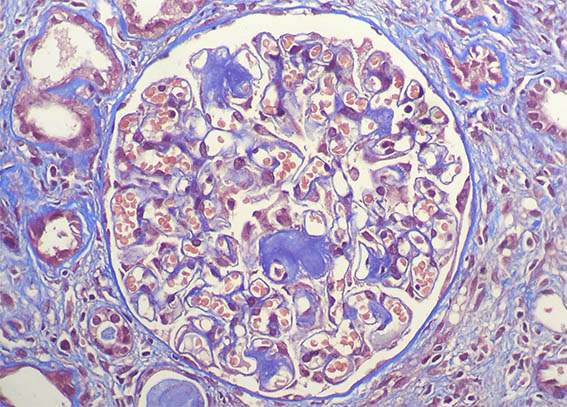

Tricrómico de Masson, X400.

Figura 8.